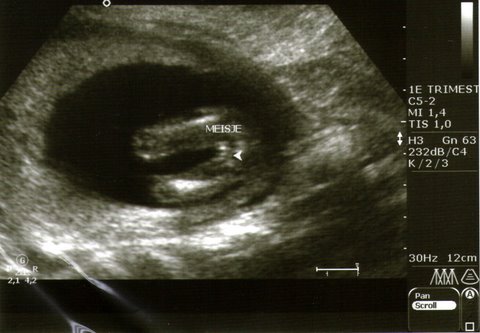

12 week scan potty shot. Sonographer adamant on gender

12 week scan potty shot. Sonographer adamant on gender from www.genderdreaming.com